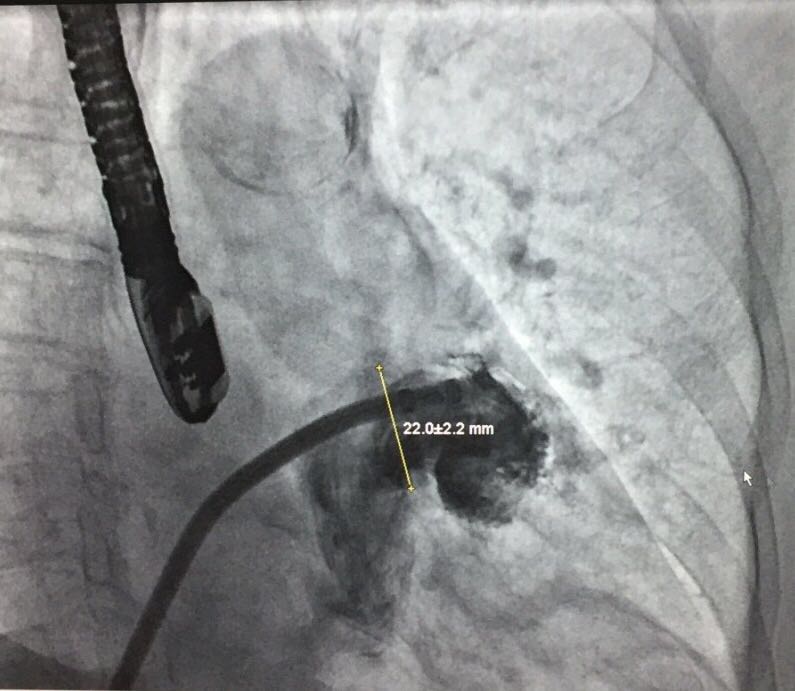

患者左心耳测量结果——开口部

当日接受手术的患者为一名74岁女性,伴有高血压,脑卒中,心律失常。入院评估CHA2DS2-VASc 评分为3分,HAS-BLED评分为4分。术中造影测量左心耳大小,锚定区测量结果为19.6±2.8mm,开口部区域测量结果为22.0±2.2mm。陶凌教授与其团队讨论后,决定选用彩神在线网信彩票-彩神通免费版下载-彩神8争霸vlll-彩神购彩购彩大厅-彩神软件陆立根免费版-彩神ll争霸3-彩神ll彩神8-彩神ll争霸彩票-拼搏在线彩神网网页版科技自主研发的LAmbre™左心耳封堵器系统2430型号的封堵器进行手术封堵。术后经造影对比及超声结果显示手术封堵效果出色,患者左心耳封堵完全,无残余分流。陶凌教授对此次LAmbre™左心耳封堵器的植入结果表示满意。陶凌教授认为LAmbre™左心耳封堵器系统在术中可轻松实现回收和再释放,便于调整最佳封堵位置,且操作可控,让左心耳封堵手术更安全、简单、有效。